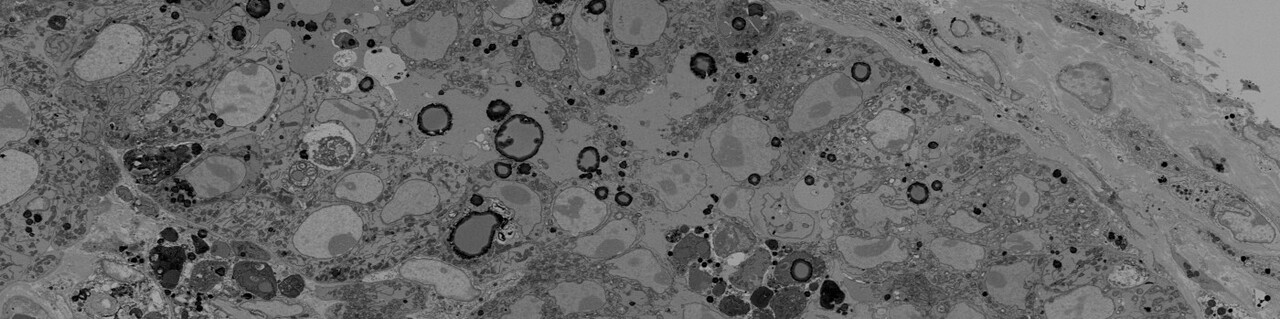

We worked together with collaborators at the Francis Crick Institute and NPL, as part of the CRUK Grand Challenges team Rosetta, and have developed a multimodal imaging pipeline that extends upon the principles of correlative light, electron, and ion microscopy (CLEIM), which combines confocal microscopy reporter or probe-based fluorescence, electron microscopy (EM), stable isotope labelling and Nanoscale secondary ion mass spectrometry (NanoSIMS). Their protocol allows an unprecedented extraction of biological information from specimens, whilst being based on a series of well-established and widely available technologies, thus allowing quick adaptation of the protocol for individual research needs. This integration provides a multifaceted view of the tissue microenvironment, capturing both the internal cellular architecture and the intricate metabolic dynamics occurring within. We tested this pipeline by imaging the incorporation of carbon from glucose into B and T cells in mouse liver tumours.